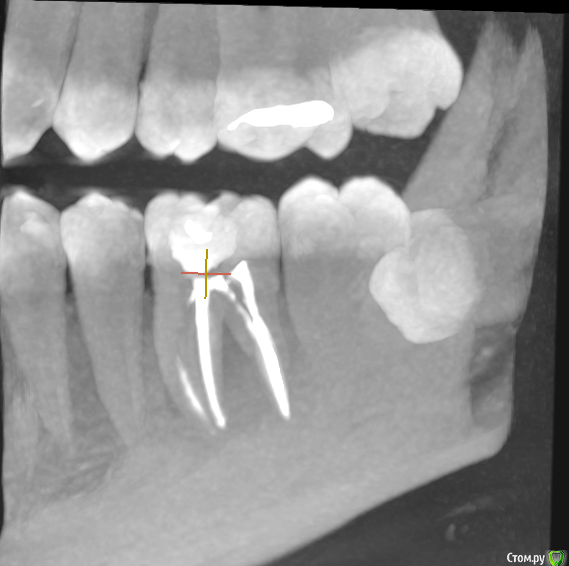

Лечили пульпит 30-го зуба, после пломбирования каналов (гуттаперчей, горячим методом) в течение пары недель (была установлена временная пломба) ощущалась боль при надавливании на зуб. Боль не прошла, пришлось распломбировать один из каналов, в котором предположительно была проблема (пластиковый "штифт", кажется).

После распломбировки одного канала ожидали полторы недели, боль осталась, на следующем приеме распломбировали все каналы, поставили временную пломбу. Перед приемом был сделан снимок 30-го зуба и двух ближайших зубов. Прошло еще пару дней, зуб все так же болит при надавливании. В чем (хотя бы ориентировочно) может быть проблема? На снимке (фото которого прилагаю) видно, что материал не выходит за верхушку корня. Трещин, кажется, тоже нет. Но в чем тогда проблема?( Если боль не пройдет, я, честно говоря, даже и не знаю, что делать...

Доброго. Речь скорее всего о 36 зубе. У Вас имеются зубные отложения (камни см.рис.) которые так же могут поддерживать воспалительный процесс влияющий на возникновение болей в зубе при надавливании. Также необходимо дифференцировать нет ли болевого синдрома из-за 38 зуба ( неправильное положение с упором в 37 ). Если даже все вышеперечисленное не является причиной болей , то может болеть зуб , иногда бывают ответвления в сторону от канала ближе к верхушке корня , которые пройти ( пролечить) крайне затруднительно , или не представляется возможным физически ....исключите сначала 2 первых пункта.